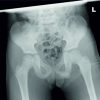

A 29-year-old female patient was admitted to our clinic for treatment in October 2023, following a severe road accident that left her with multiple injuries. She sustained several fractures, along with 3rd° burns that covered her entire right lower limb and right flank, which represented 20% of her total body surface area. Despite the surgical debridement and escharotomies, the right leg’s soft tissues became full-thickness necrotic, necessitating the decision to amputate the inferior limb (Fig. 1).

The stump was kept long enough to allow for the use of a prosthetic, but definitive coverage was not possible due to the burn extension. As a result, wounds were temporarily covered with dermal substitutes, such as Integra® and Pelnac™. Only the tip of the stump was repaired with a meshed skin graft (Fig. 2). Antibiotic therapy was deemed necessary based on the findings of the swab test; however, blood cultures and bacteriuria screening remained negative throughout the entire hospitalization period. The wounds were then covered with homologous skin grafts from a cadaver bank (Fig. 3) and NPWT was initiated by applying Suprasorb® R CNP EasyDress® by Lohmann and Rauscher on the grafts at −80 mmHg.